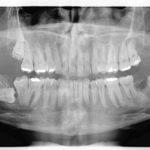

Parestesia differita: dopo l’estrazione di un dente del giudizio

Riassunto

In seguito a una lesione del nervo alveolare inferiore, nella maggior parte dei casi, la comparsa di un’alterata sensibilità inizia immediatamente dopo l’intervento chirurgico, altre volte...